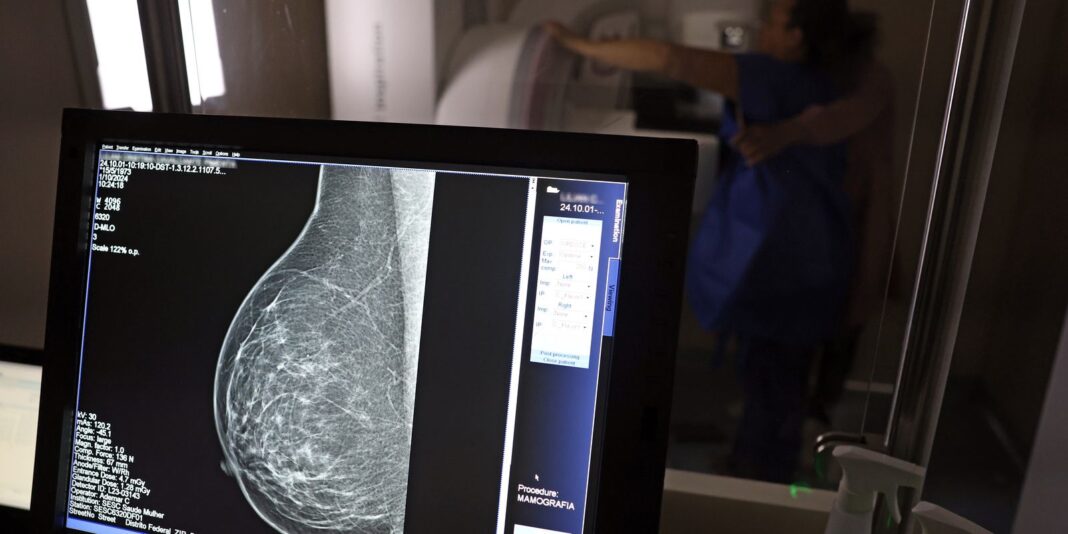

O direito já estava incluído na CLT desde 2018. A partir de agora, as empresas passam a ser obrigadas a divulgar essa informação, além de outras relacionadas a campanhas oficiais de vacinação contra o HPV e sobre o acesso a serviços de diagnósticos de cânceres de mama, próstata e de colo do útero.

O texto estende o uso das folgas também para a realização de exames preventivos do HPV, além dos de câncer que já estavam previstos na legislação anterior. A a Lei 15.377 foi sancionada pelo presidente Luiz Inácio Lula da Silva, e publicada na edição do Diário Oficial da União (DOU).